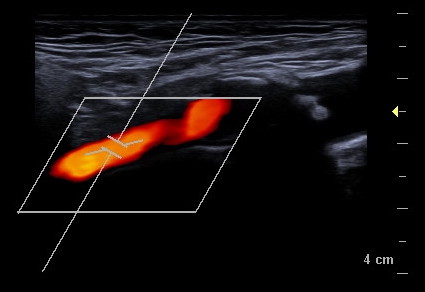

Gefäßdarstellung mittels Ultraschall

Bei der Doppler-Duplex-Sonographie der Halsgefäße wird untersucht, ob Verkalkungen (Plaques) vorliegen, und ob es dadurch zu Verengungen (Stenosen) kommt.

Neben dem Aussehen der Plaques wird die lokale Flussgeschwindigkeit des Blutes beurteilt: Je schneller die Flussgeschwindigkeit, desto hochgradiger die Stenose.